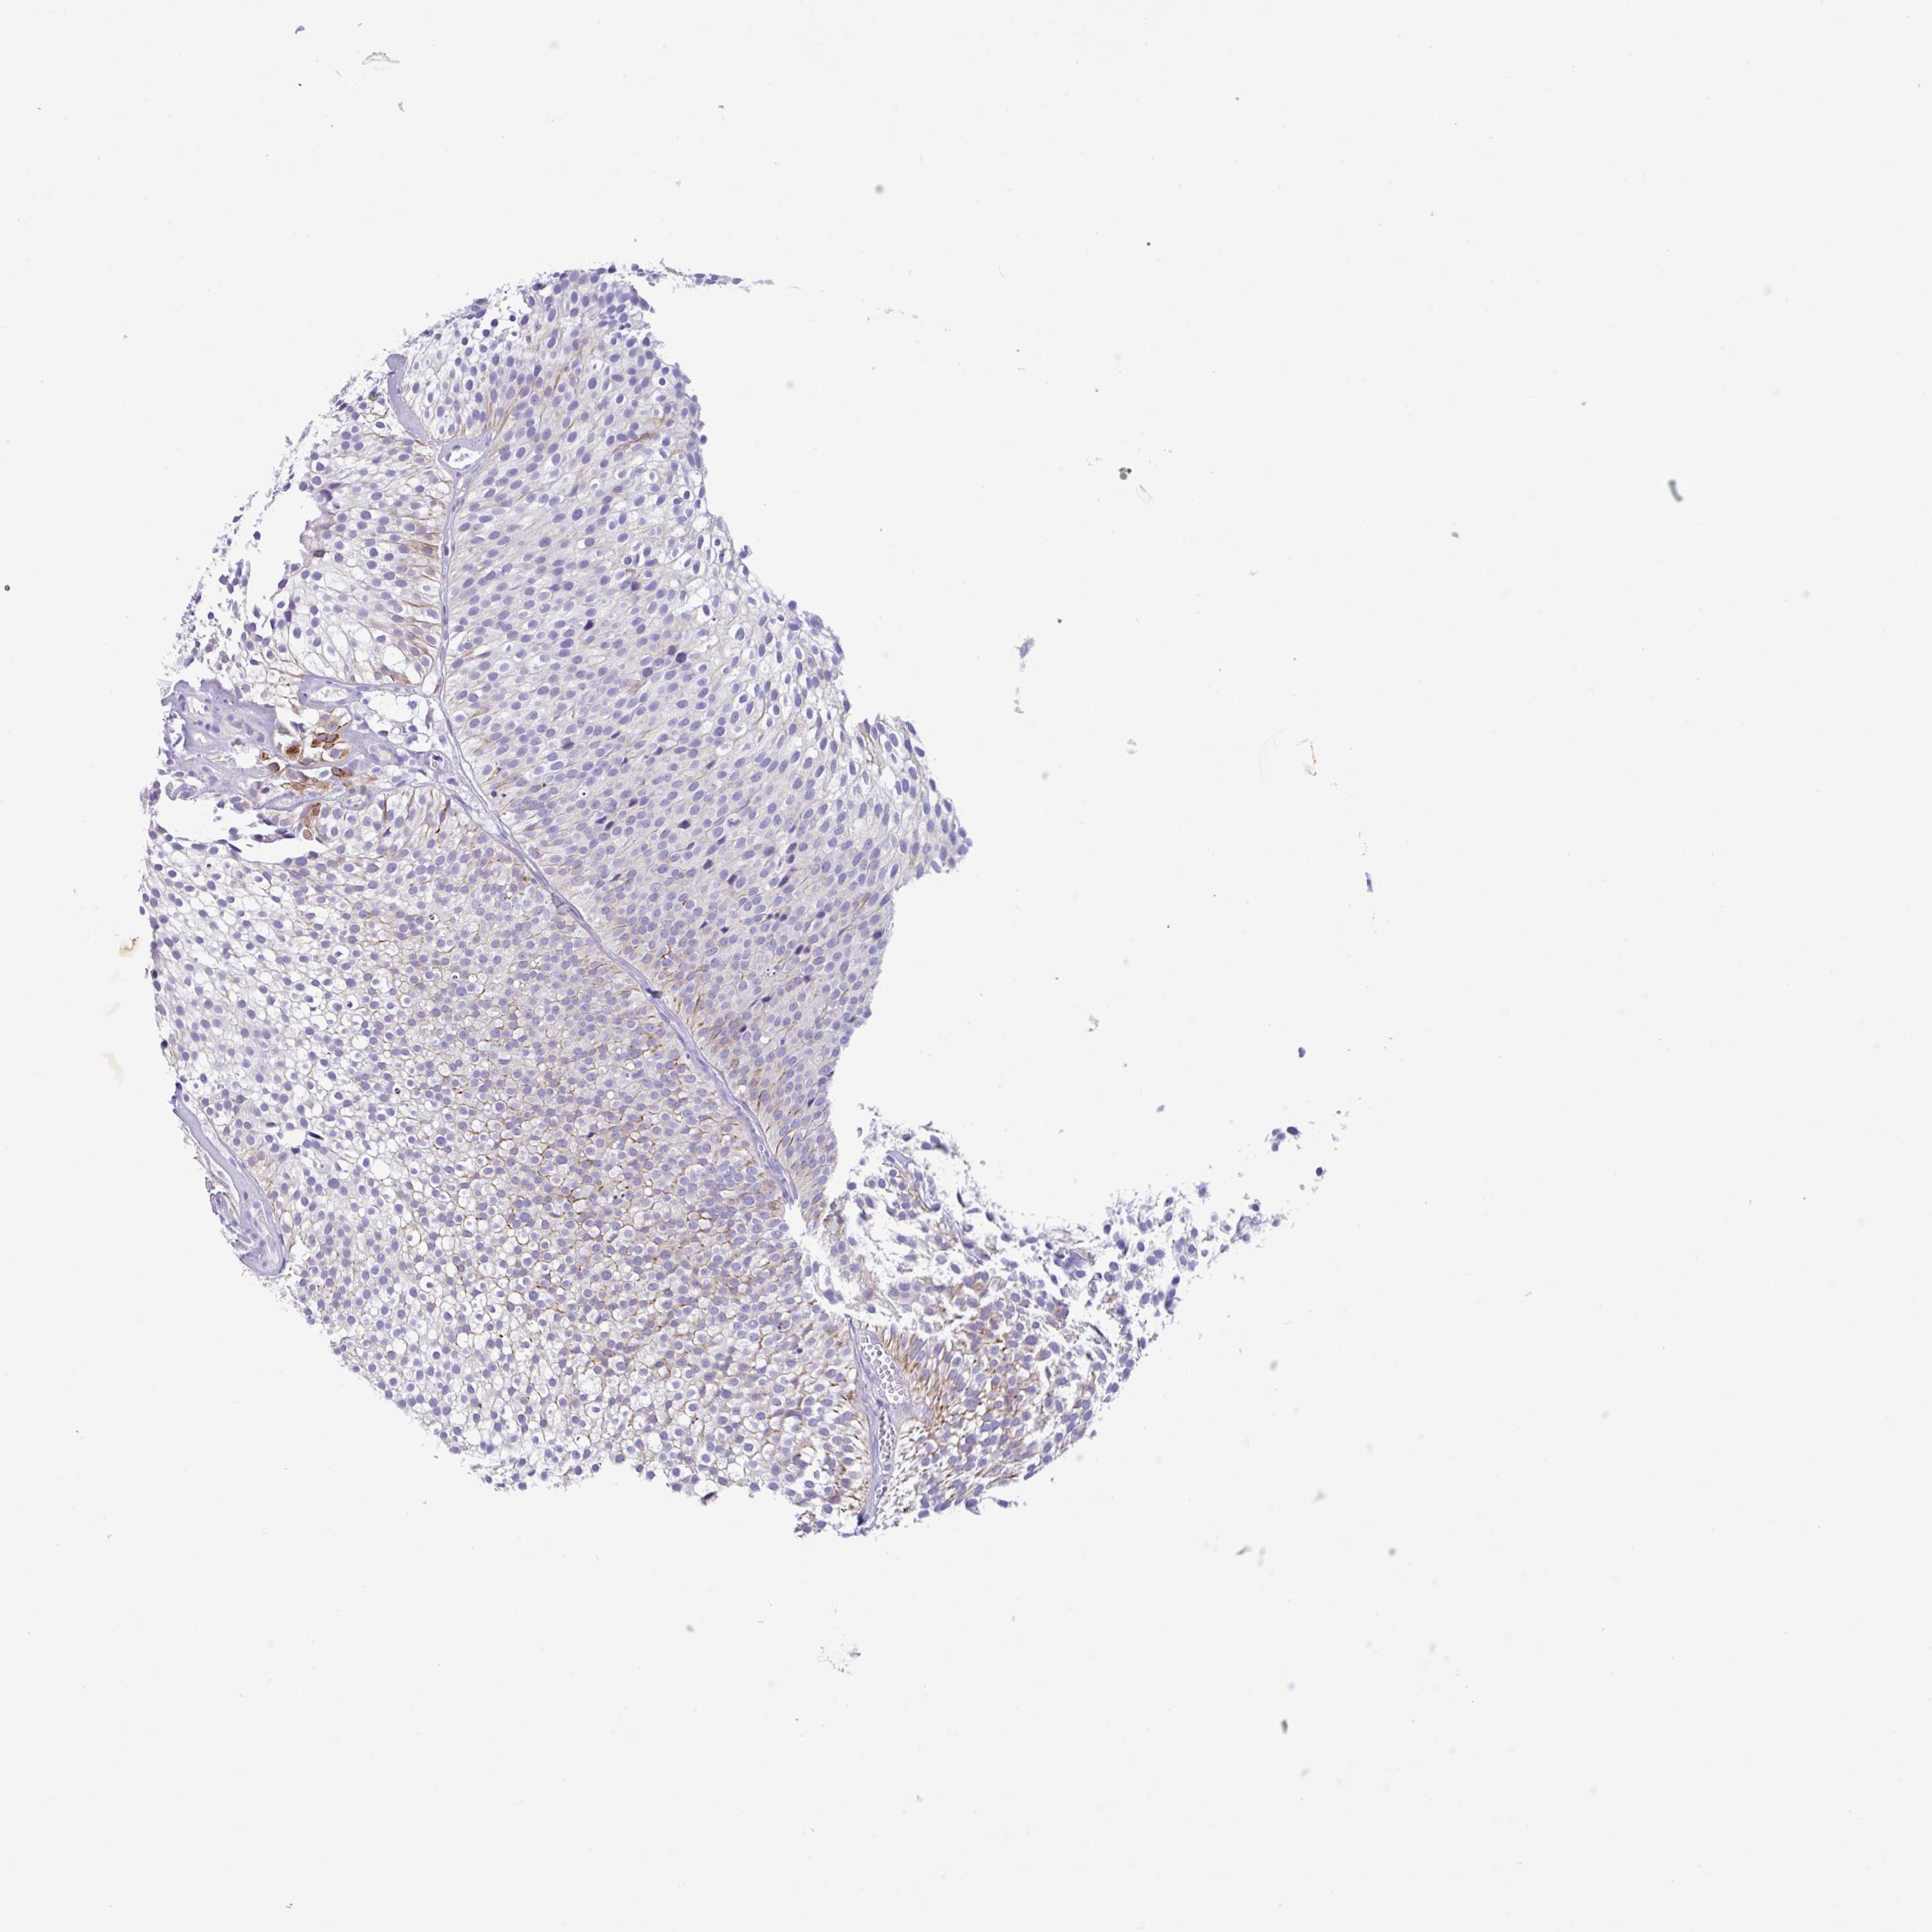

UROTHELIAL CANCER - Protein expressioni

A mouse-over function shows sample information and annotation data. Click on an image to view it in a full screen mode. Samples can be filtered based on level of antibody staining by selecting one or several of the following categories: high, medium, low and not detected. The assay and annotation is described here.

Note that samples used for immunohistochemistry by the Human Protein Atlas do not correspond to samples in the TCGA dataset.

Antibody stainingi

Antibody staining in the annotated cell types in the current human tissue is reported as not detected, low, medium, or high, based on conventional immunohistochemistry profiling in selected tissues. This score is based on the combination of the staining intensity and fraction of stained cells.

Each image is clickable and will lead to virtual microscopy that enables deeper exploration of all samples and also displays staining intensity scores, fraction scores and subcellular localization as well as patient and tissue information for each sample.

Antibody HPA044748

Antibody HPA050397

Urothelial carcinoma, High grade

Urothelial carcinoma, Low grade